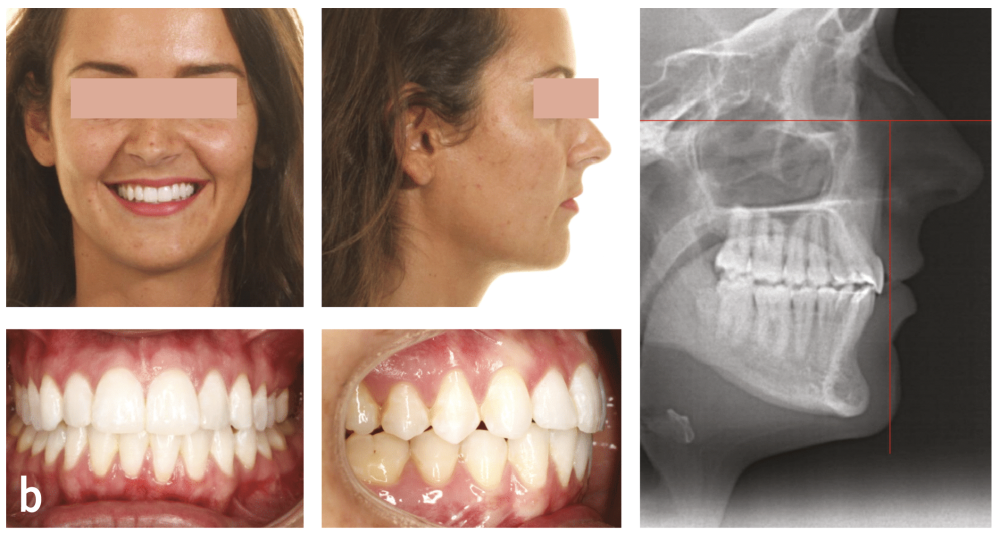

Durant son intervention, le Dr Marinetti a développé les trois bases de l’orthodontie : stabilité, esthétique et fonction. Pour lui, il ne faut pas hésiter à aller vers la chirurgie maxillo-faciale dès que nécessaire, car l’harmonie de la face et le sourire sont intimement liés.

La céphalométrie aide au diagnostic. De manière simplifiée, sur une téléradiographie de profil, le plan de Francfort puis le plan antérieur de Cocconi, qui passe par le point le plus antérieur de l’os maxillaire, sont tracés ; la ligne qui passe par la face vestibulaire de l’incisive centrale maxillaire doit être tangente à ce plan (fig. 1). L’incisive centrale mandibulaire doit être au contact de son antagoniste. Si, à la suite de la simulation de cette analyse, l’incisive du bas est en dehors de l’enveloppe osseuse, cela implique le choix thérapeutique d’une chirurgie orthognatique du maxillaire et/ou de la mandibule (fig. 2).